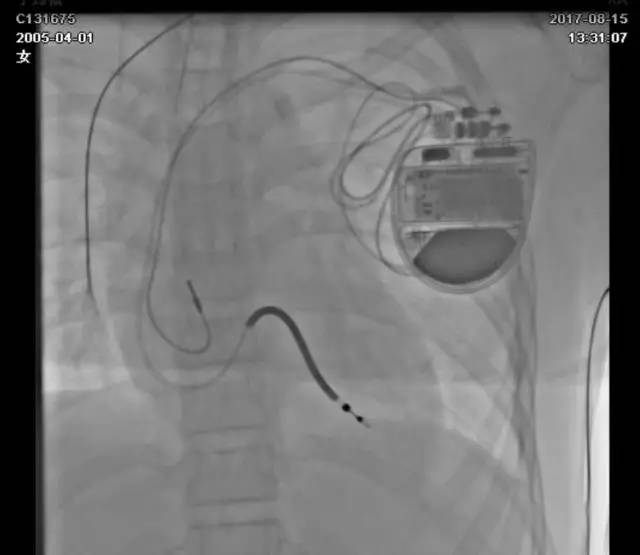

手术时间:2017-8-15

经静脉放置起搏和除颤导线:

心房电极位置为右心耳,右室除颤电极放置于右室低位间隔,由于患者年纪小,右房、右室除颤导线预留半圈电极导线长度。

术中影像